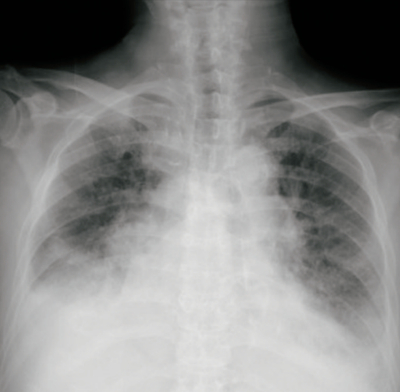

血液所見:赤血球350万、 Hb 8.8 g/dL、Ht 28%、白血球 13,100、血小板 21万。血液生化学所見: AST 99 U/L、ALT 31 U/L、LD 659 U/L(基準 120〜245) 、クレアチニン 1.4 mg/dL、血糖 128 mg/dL、脳性ナトリウム利尿ペプチド〈BNP〉2,920 pg/mL(基準 18.4以下)。CRP 2.2 mg/dL。胸部エックス線写真を別に示す。